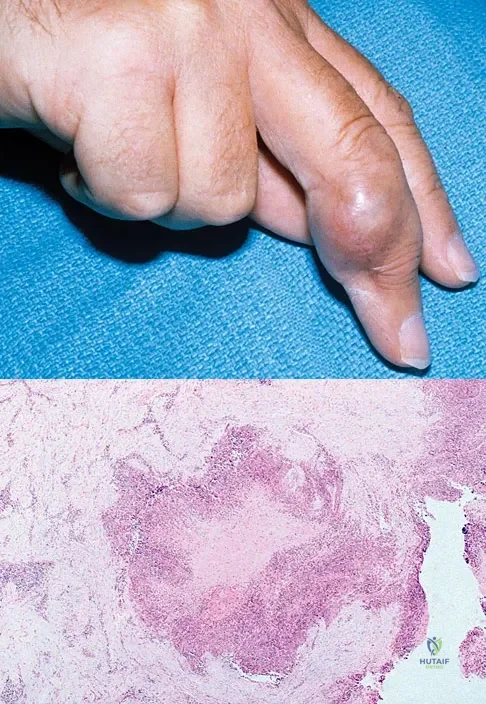

Figure 18a shows the clinical photograph of a 31-year-old man who has a slowly growing nodule on his right middle finger. It is minimally tender, and there is no erythema on examination. A biopsy specimen is shown in Figure 18b. What is the most likely diagnosis?

Explanation